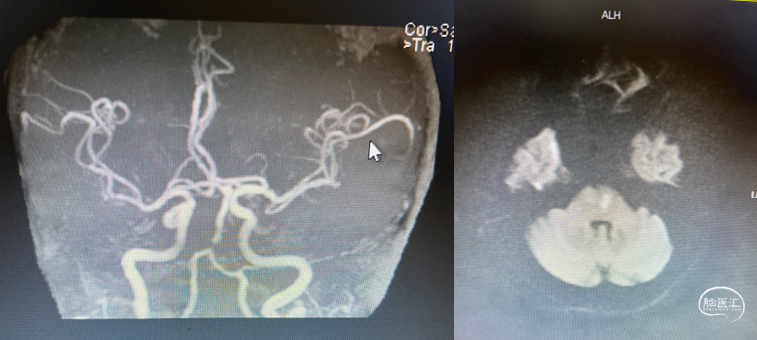

CTA

MRA

重要影像结论:MRA见基底动脉起始部重度狭窄,较前相比似有加重;DWI见点状缺血灶。